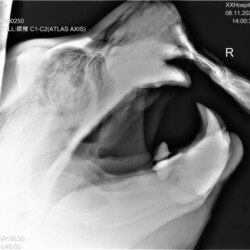

Обученный зверь по команде замер на несколько секунд и позволил сделать себе снимок челюсти

Светлана – кипер, рабочий по уходу за животными. Она уже два года проводит тренинги с гигантским зверем: вместе с коллегами чистит сивучу зубы, промывает ротовую полость, учит несложным командам. Это не дрессура ради шоу – благодаря занятиям животное привыкает к людям и позволяет проводить с ним различные манипуляции, прежде всего, медицинские. Недавно сивучу сделали рентген: обученный зверь по команде замер на несколько секунд и позволил сделать себе снимок челюсти переносным аппаратом.

– Дается команда, сотрудники прикасаются к носу и нижней челюсти сивуча, как бы фиксируют его голову. Мы не держим его, а даем ощущение контакта. Так и получилось сделать снимок, – рассказывает Светлана.

Рентген показал проблемы с клыками и в целом с верхней челюстью. По словам Светланы, у старенького сивуча и так осталось четыре зуба вместо 25-ти. Но особого дискомфорта ему это не доставляло – рыбу сивучи не жуют, а заглатывают. Недавно воспаление перешло на костную ткань.

– Мы можем сказать: периодонтит и пульпит верхних клыков, пародонтит возле верхних и нижних клыков. Для более точных диагнозов нужно делать еще снимки, но это технически невыполнимо, потому что мы не можем расположить аппарат под нужным углом из-за решеток. Также есть подозрение на остеомиелит верхней челюсти, – говорит главный ветеринарный врач зоопарка Алла Тыкманова.